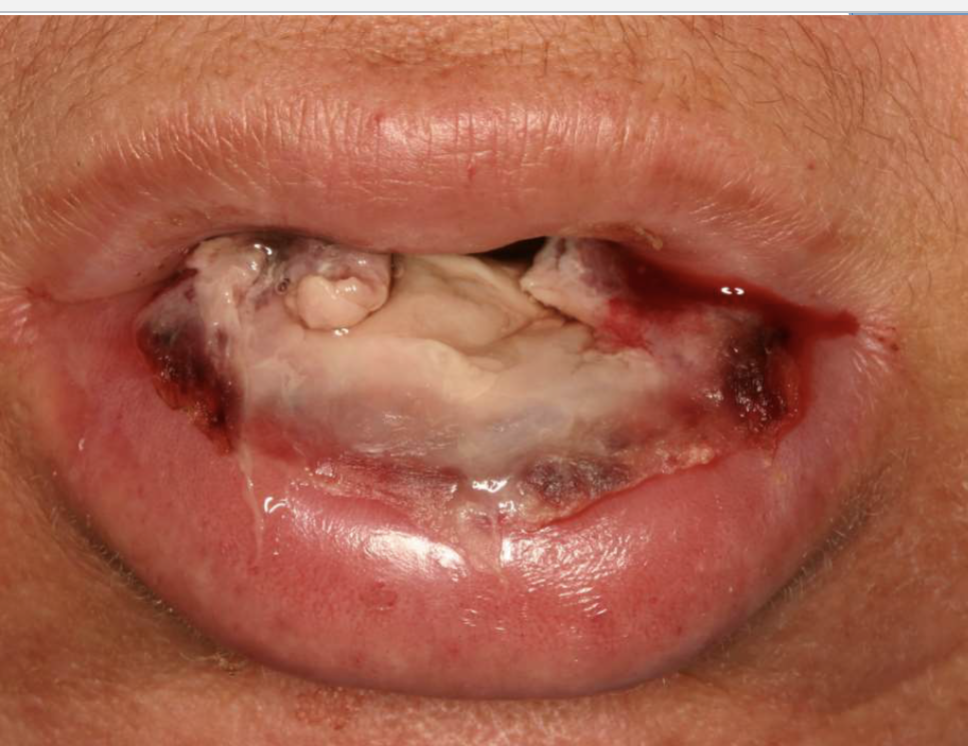

what is this

exfoliative cheilitis: excess production + desquamation of keratin

exfoliative cheilitis affects men or women more

women